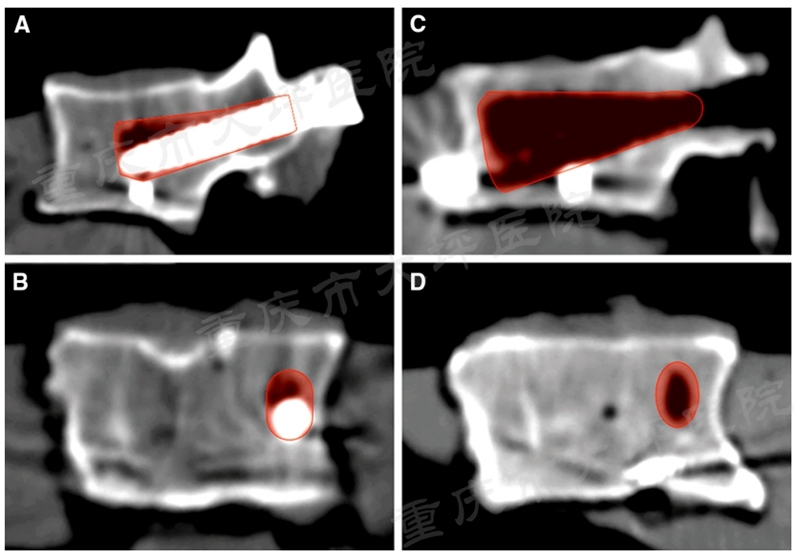

课题组前期的回顾性病例对照研究证实,单侧使用PMMA螺钉(2颗)与双侧使用PMMA螺钉(4颗)具有相近的临床疗效,成功将PMMA螺钉使用的推荐数量从4颗减少为2颗。进一步观察发现,普通椎弓根螺钉失效模式为“雨刮效应”(图2)。

图2 CT扫描示意“雨刮效应”

骨水泥增强椎弓根螺钉后,由于骨-钉界面的应力分布特征被人为改变,失效模式与普通螺钉相比也发生了变化,将其称为“反雨刮效应”(图3),该现象的生物力学机制尚不清楚。课题组敏锐的发现,在其背后可能蕴含着合理应用PMMA螺钉的关键线索。

图3 “反雨刮效应”示意图